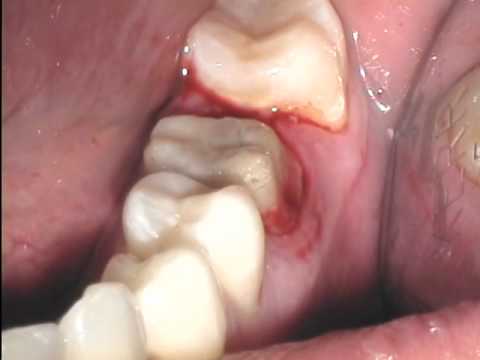

Astringedent™ X, Spritzen - IndiSpense-Spritze 30 ml

Anästhetika / Pharmazeutika / Retraktion / 143111 | Ultradent Products - UP 690

143111

| Ultradent Products - UP 690

Beschreibung:

12,7 %-ige Eisenlösung. Behandelt wirksam schwer stillbare Blutungen. Weniger ätzend als andere Eisensubsulfatlösungen.

Kategorie:

Anästhetika / Pharmazeutika

/

Retraktion